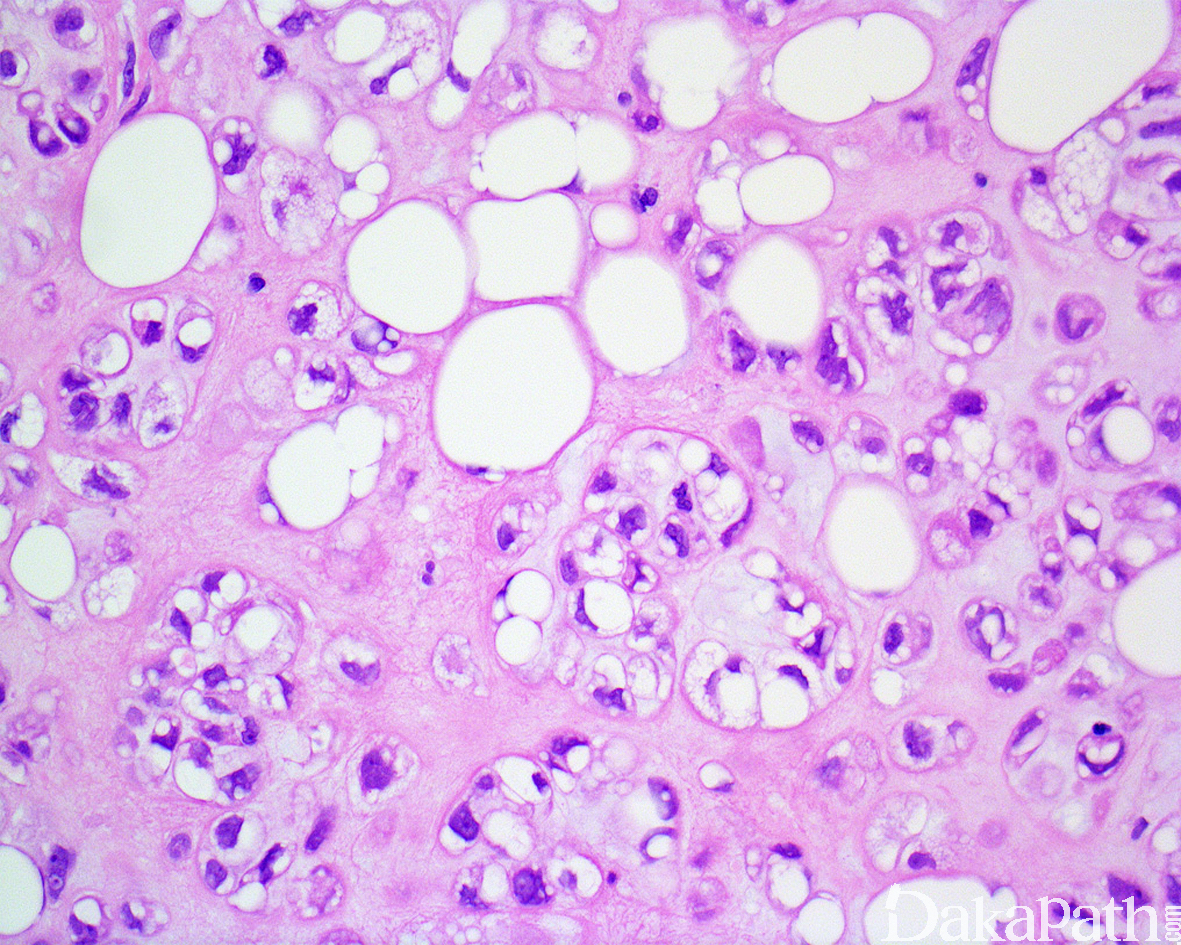

镜下肿瘤边界清楚,由薄的纤维性间质分隔呈小叶状;

小叶由位于软骨黏液样基质内的片状、巢状或索状圆细胞以及数量不等的成熟脂肪细胞组成;

圆细胞胞浆空泡状或嗜酸性颗粒状,有时可见多个空泡形成并挤压核形成核切迹从而类似于脂肪母细胞;

瘤细胞核卵圆形或肾形,核染色质均匀细腻,核仁不明显或含小的嗜碱性核仁,无核异型性,核分裂像罕见;

基质呈软骨黏液样或黏液玻璃样变样,围绕嗜酸性或空泡状细胞周围形成类似于软骨的陷窝;

肿瘤内血管丰富(各种口径大小的血管均可见,较小的血管常见血栓形成),常见灶性出血和纤维化,偶见钙化或骨化以及慢性炎细胞浸润。